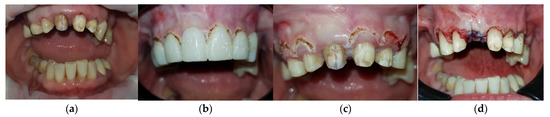

2. Case Report